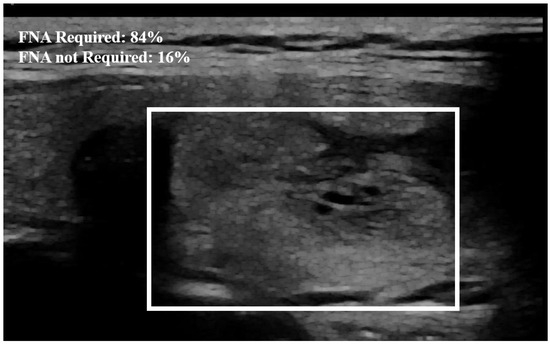

Examples of our method for the classification of the thyroid nodule images are shown in Figure 5 and Figure 6. The results of the proposed model with and without data augmentation are shown in Table 2. We can conclude that adding synthesized images improved the performance of the model quite effectively. We compared our proposed method with different deep learning architectures (Table 3). We began with experiments using a simple CNN and then fine-tuned pre-trained features to capture specific patterns relevant to our task. This approach led to improved performance compared to training a model from scratch. We conducted numerous experiments on the combination of focal loss parameters ( α and γ ) and different deep learning architectures. For our classification, α was set to 0.25 for the negative class and 0.75 for the positive class, depending on the class imbalance. Typical values for γ were in the range [ 0 , 5 ] . We experimented with several values of γ within this range for different models listed in Table 3, and γ = 3.5 was empirically found to be the optimal value.

The proposed method outperformed the other classic approaches. This is due to the fact that the incorporated attention modules are playing an efficient role in extracting the most important features. The other models did not perform well compared to the proposed approach, most likely due to over-fitting. We observed that the other models ended up memorizing some abstract patterns and were highly sensitive to random fluctuations. Hence, the lowest F1-score on this classification task was 0.79 , obtained from the predictions done by the simple CNN network. The proposed method only misclassified 4 images out of the 64 test set images, as illustrated by the confusion matrix in Figure 7. During the training session of the model, 20% of the dataset is automatically split for the validation process. We also assessed the model’s generalization capacity on unseen data. In the test set dataset, the model maintained high scores, achieving an average accuracy of 0.94 and a F1-score of 0.93 . These results indicate the robustness and effectiveness of the model’s performance in accurately classifying thyroid nodules. The model’s performance evaluation was conducted on individual image database centers to assess the portability of our approach. The average accuracy and F1-score for the test set from the Hospital of Bastia database were 0.87 and 0.89 , respectively. Similarly, for the test set from the Hospital of Dijon database, the average accuracy and F1-score were 0.90 and 0.86 , respectively. However, the mixed test set from both centers achieved the highest performance, with an F-score of 0.93 , as shown in Table 3. We also compared the proposed method with previous studies, as detailed in Table 4. The results demonstrate that our approach provides competitive performance in the classification of thyroid nodules, achieving high accuracy and reliability compared to other existing methods. For instance, in Figure 6, the probability of the nodule requiring FNA based on the model output is established to be 84%. Then, according to our model, this nodule is at high-risk level and fine needle aspiration is recommended.

Figure 6. Example of nodule classification. The probability established by the model from the image that the nodule needs FNA is equal to 84%. The surrounding rectangle indicates the location of the nodule.